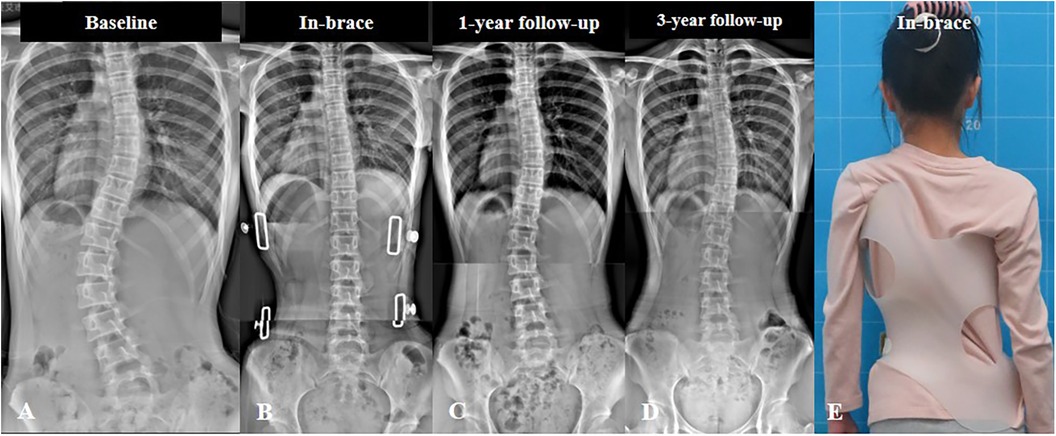

العلاج المبكر يشمل غالبًا برامج العلاج الطبيعي المخصصة لاضطرابات العمود الفقري، وتمارين تصحيحية مصممة لتقوية العضلات ودعم توازن الجسم. في بعض الحالات، قد يتم استخدام حزام تقويم العمود الفقري لمنع زيادة الانحناء مع نمو الطفل.

الأشعة الدورية: لتحديد زاوية الانحناء ومتابعة أي تغير.

الحزام التصحيحي عند الحاجة: في بعض الحالات، يساعد على تقويم العمود الفقري ومنع زيادة الانحناء.

هل يمكن حصر الانحناء باستخدام الحزام فقط؟

الحزام غالبًا يستخدم للانحناءات المتوسطة أو عندما يكون الطفل في مرحلة نمو نشطة. مع التمارين العلاجية، يمكن غالبًا تقليل الانحناء إلى مستويات آمنة.

الانحناءات الصغيرة في العمود الفقري بين 10 و25 درجة تمثل فرصة ذهبية للتدخل المبكر قبل أن تصبح التغيرات الهيكلية أكثر صعوبة في التصحيح. الدراسات الحديثة تؤكد أن أفضل النتائج تتحقق عند بدء العلاج في هذه المرحلة، سواء من خلال العلاج الطبيعي المخصص، تمارين تقوية العضلات، أو استخدام الحزام التصحيحي عند الحاجة.